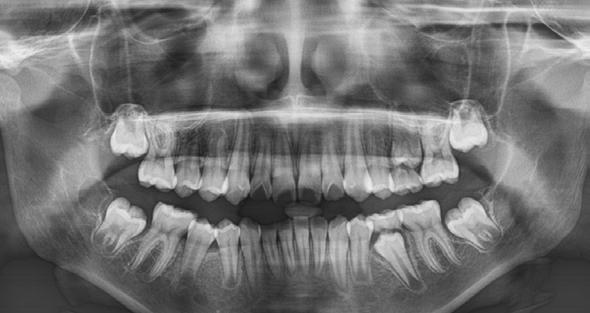

Introducción: La sinusitis odontogénica es una afección del seno maxilar ocasionada por el acceso de bacterias provenientes de los ápices de uno o más órganos dentales con proceso infeccioso activo, favoreciendo la inflamación de la mucosa, provocando una alteración en su producción y la presencia de otros síntomas. El tratamiento de primera elección es farmacológico y en caso de no presentar mejoría se realizará algún procedimiento quirúrgico según el estado en el que se encuentra el órgano dental comprometido y gravedad del padecimiento.

Materiales y métodos: Para este trabajo se realizó una investigación detallada de diversas fuentes de investigación como lo son pubmed, Science direct, entre otras y para el apartado del caso se decidió hacer un tratamiento mediante la comunicación oroantral Caso clínico: Paciente femenino de 49

años de edad, la cual es remitida por especialista en endodoncia por referir rinorrea, cefaleas y estornudos recurrentes con un año de evolución, ya tratada por otorrinolaringología sin mejoría.

Radiográficamente se observa lesión periapical con cercanía a seno maxilar por lo que se realiza extracciones de segundo y tercer molar superior derecho y limpieza a través de comunicación oroantral y cierre con la bola adiposa de Bichat.

Los signos radiográficos compatibles con la SO incluyen más de 6 mm de engrosamiento de la mucosa en senos maxilares en adultos (> 4 mm en niños), más del 33% de pérdida del volumen del espacio aéreo dentro de los senos maxilares o zonas radiopacas y niveles hidroaéreos en cualquiera de los senos paranasales. La radiografía occipitomentoniana o Watters puede ser útil en la detección de adultos y niños mayores de 1 año, pero tienen una sensibilidad inadecuada por lo que el estudio de elección es la tomografía computarizada de senos paranasales. El gold standard es la tomografía computarizada (TC) de cavidades paranasales, que identifica todo tipo de lesiones.2,8

derecho (Figura 1). Especialista en endodoncia solicita cone beam en donde se visualiza lesión periapical extensa que involucra segundo y tercer molar ipsilateral y engrosamiento de la mucosa del seno maxilar sugerente de sinusitis maxilar crónica y su cercanía

con el tercer molar de dicha estructura (Figura 2).

Figura 1. Fotografía oclusal.

Figura 2. Cone Beam en corte sagital sectorial de segundo y tercer molar.

En un estudio en Latinoamérica por la doctora Novoa, se describe el aumento en los ultimos años de cone beam que tiene una calidad de imagen similar a la tomografía computarizada, con la ventaja de emitir una menor radiación, motivo por el cual fue nuestro elemento diagnóstico en este caso. Al contrario de la radiografía dental que, aunque es el examen radiológico

más usado para detectar periodontitis apical, pero al ser una imagen en 2 dimensiones donde se genera una superposición de estructuras, con una alta tasa de falsos negativos, mientras que la ortopantomografía nos permite ver la neumatización del seno, la relación de los dientes y el seno maxilar, pseudoquistes, restos radiculares y cuerpos extraños intrasinusales, pero también es una imagen en 2 dimensiones.20